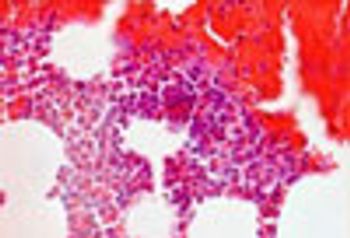

Mycobacterium avium complex enteritis; cytomegalovirus; Whipple disease; sprue: what endoscopic findings reveal the cause of worsening diarrhea in this HIV-infected man with a CD4 cell count of 32/μL?